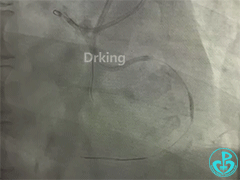

左冠造影:

导丝怎么扩收藏:器械难以通过的CTO病变之技术图谱_https://www.jmylbn.com_新闻资讯_第2张

导丝怎么扩收藏:器械难以通过的CTO病变之技术图谱_https://www.jmylbn.com_新闻资讯_第3张

导丝怎么扩收藏:器械难以通过的CTO病变之技术图谱_https://www.jmylbn.com_新闻资讯_第4张

导丝怎么扩收藏:器械难以通过的CTO病变之技术图谱_https://www.jmylbn.com_新闻资讯_第5张